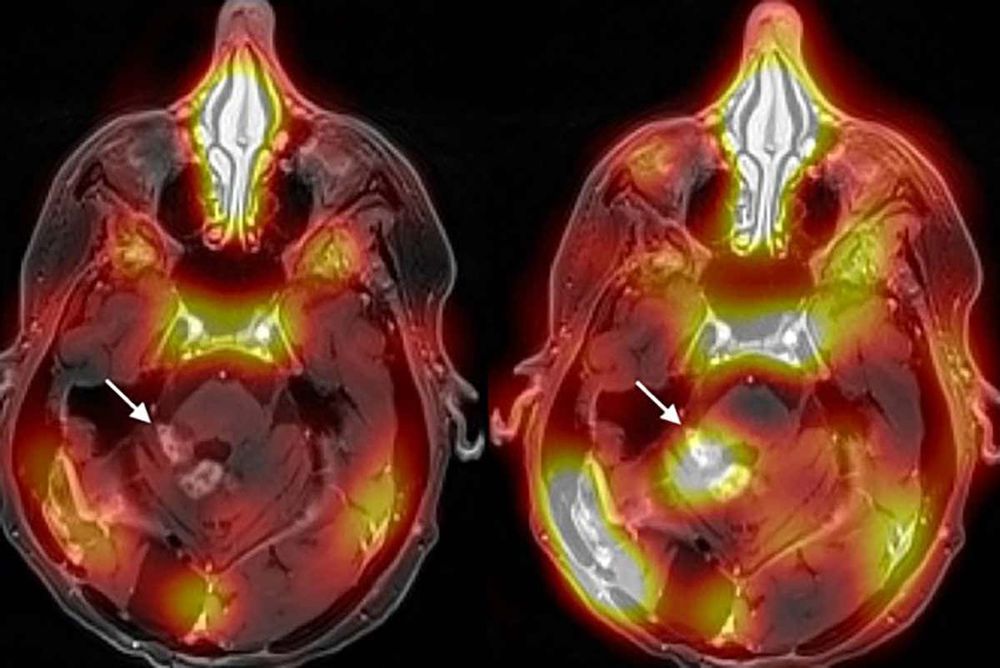

Depuis des décennies, les scientifiques tentent de faire passer des médicaments à travers cette barrière. L'une des principales approches, appelée MR-guided focused ultrasound (MRgFUS), consiste à injecter de minuscules bulles dans le sang, puis à diriger des faisceaux d'ultrasons vers la région du cerveau visée. Les ultrasons font vibrer les bulles, ce qui élargit l'espace entre les cellules de la paroi des vaisseaux sanguins.

Cette méthode a déjà été présentée auparavant, mais son efficacité n'avait jamais été démontrée jusqu'à présent. Nir Lipsman, du Sunnybrook Research Institute de Toronto (Canada), et ses collègues, ont utilisé cette technique pour administrer le traitement anticancéreux Herceptin aux tumeurs qui s'étaient propagées au cerveau de quatre femmes atteintes initialement d'un cancer du sein.

Après avoir reçu des traitements toutes les trois semaines, jusqu'à six fois, leurs cancers ont diminué de 21% en moyenne. Le médicament avait été marqué avec un composé légèrement radioactif, ce qui a permis de montrer, par IRM, qu'il avait bien atteint leurs tumeurs cérébrales. « La réduction de la taille des tumeurs est prometteuse mais doit être interprétée avec prudence car des recherches supplémentaires à plus grande échelle sont nécessaires », explique le Dr Rossanna Pezo, oncologue médicale au Odette Cancer Centre à Sunnybrook.